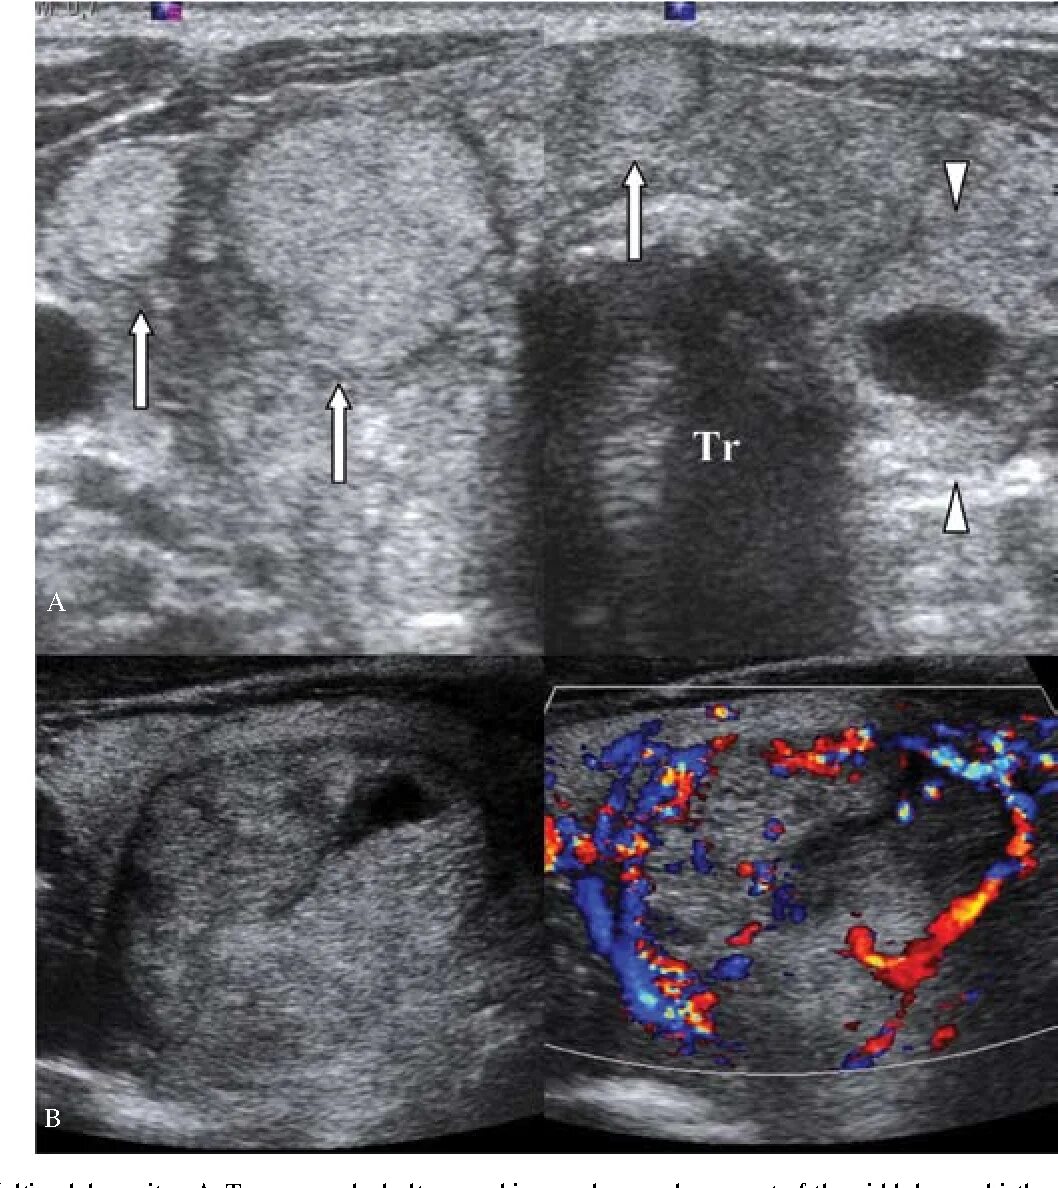

Белое пятно на узи